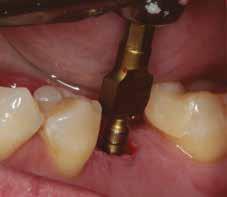

A behelyeztt implantátum primer stabilitását megfelelőnek ítéltük (kb. 40 Ncm) az azonnali terheléshez (9. kép).

Az extrakciót megelőző szituációs lenyomat alapján gyári, titán, ideiglenes abutment felhasználásával, a szék mellett készített, csavaros rögzítésű, azonnali akrilát ideiglenes koronával láttuk el, melyet 20 Ncm nyomatékkal rögzítettünk (10. kép). Az azonnali terhelés szabályainak megfelelően, az ideiglenes korona nem volt kontaktusban a szomszédos és az antagonista fogakkal.

6. kép: Implantátum-ágy preparáció. 7. a–b. képek: Implantátum behelyezés. 8. kép: A behelyezett implantátum. 10. a–b képek: Azonnali ideiglenes korona készítése. 9. kép: Megfelelő primer stabilitás.